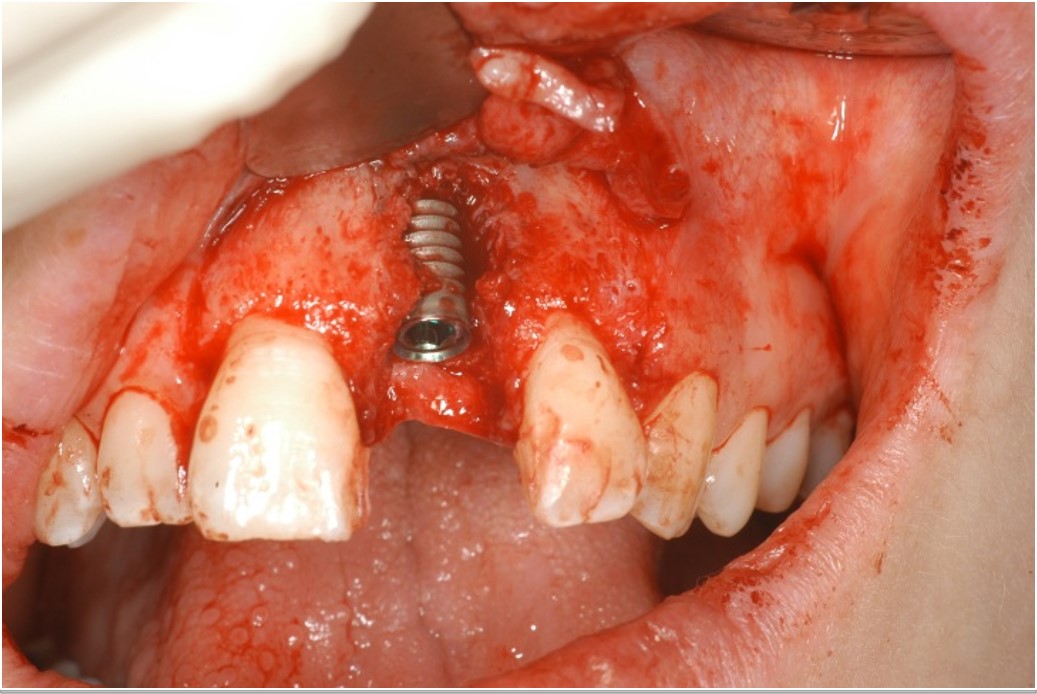

04/12 - Implant with extended dehiscence defectTreatment of dehiscence defect with cerabone® & Jason® membrane - Dr. M. Steigmann

05/12 - Covering of implant with autologous bone chipsTreatment of dehiscence defect with cerabone® & Jason® membrane - Dr. M. Steigmann